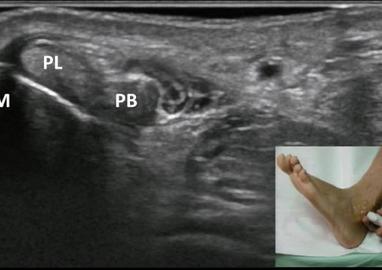

Figure 7 From Ultrasound Of Peroneal Tendons Semantic Scholar - Normal ultrasound images are shown concurrently.

Presentation1 Pptx Ultrasound Examination Of The Ankle Joint - There are actually two peroneal tendons.